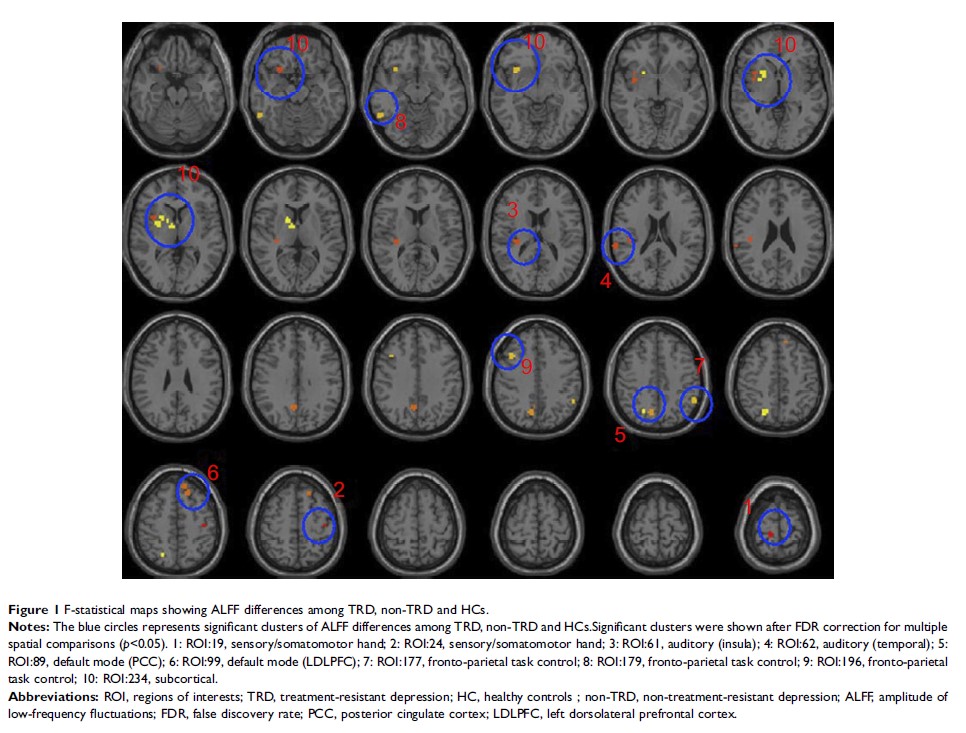

治疗抵抗性与非治疗抵抗性抑郁症患者时低频波动幅度的变化